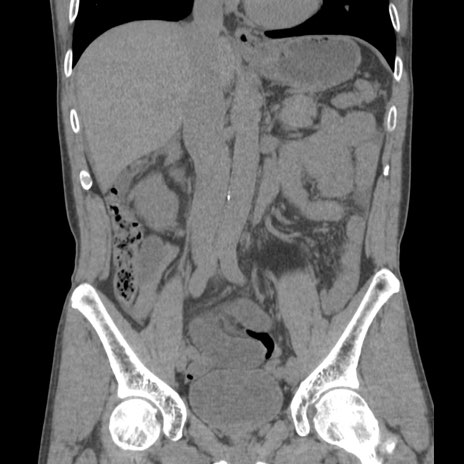

症例56 CT(冠状断像)

横断像